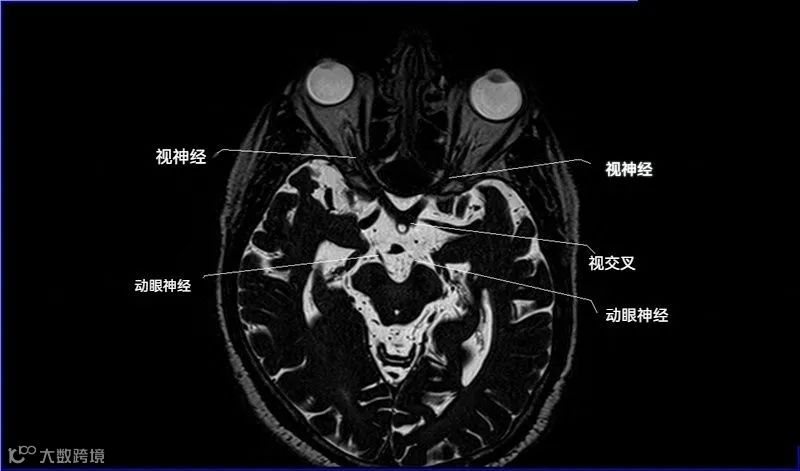

十二对脑神经口诀

一嗅二视三动眼,四滑五叉六外展,

七面八听九舌咽,迷走及副舌下全。